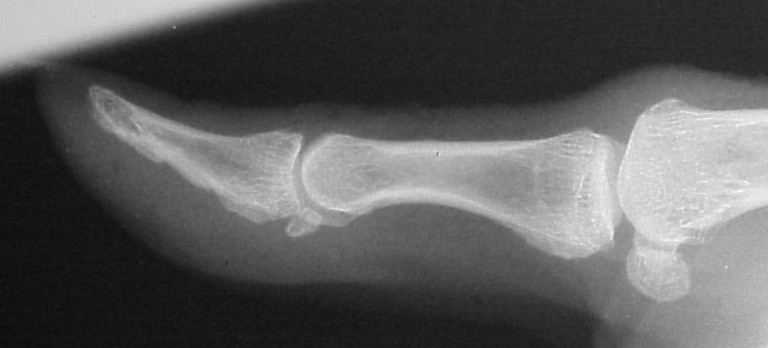

Plain films showed resorption of the distal two thirds of the distal phalanx:

Comparison views of the opposite side: